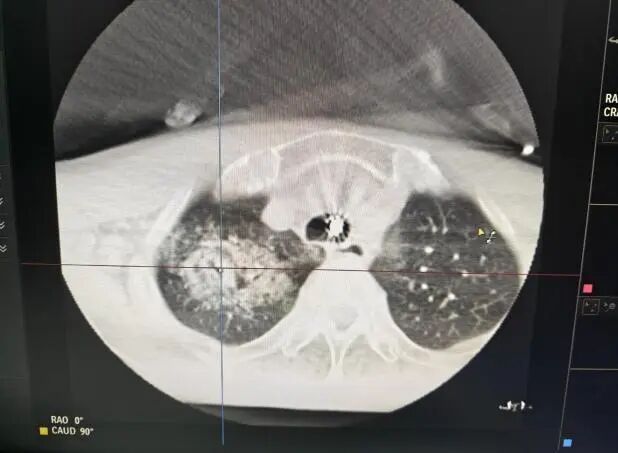

2、通过机器人气管镜,送入冷冻导管,固定后行 DSA 影像系统(CBCT)观察导管位置是否合适。

3、冷冻消融:进行冷冻操作,总时长约 30 分钟左右。